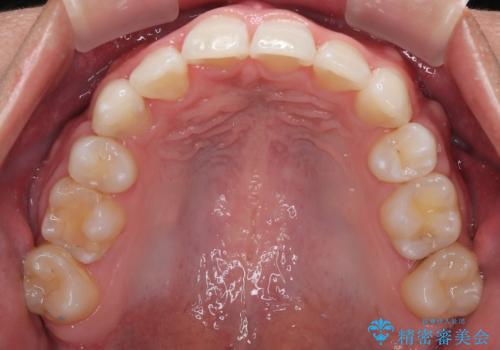

治療後には、デコボコと正中の位置が改善し、見た目だけでなく歯磨きがしやすい清潔なお口の環境を手に入れました。